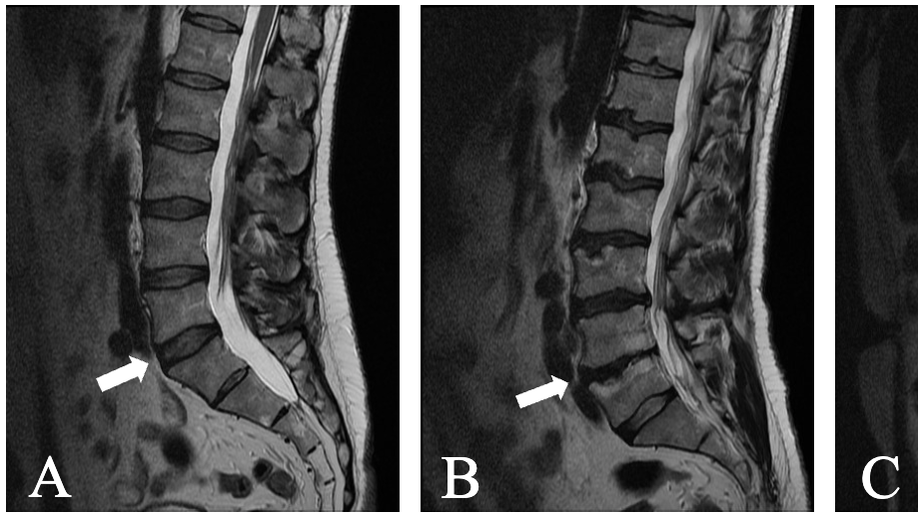

Background: The temporal sequence of lumbar spine degeneration (trajectory) is difficult to characterize due to limited availability of longitudinal imaging data. The aim of this cross-sectional study was to discover degeneration trajectories and their clinical relevance by applying an innovative computational approach to an extensive dataset from chronic low back pain patients. Methods: Clinical MRI exams from 423 patients in the comeBACK study were graded for disc degeneration, facet osteoarthritis, and other pathoanatomical features. We then trained an event-based model, which is specifically designed to infer longitudinal trajectories from cross-sectional data to model spine degeneration trajectory subtypes. The clinical significance of the identified trajectories was assessed using propensity score matching of trajectory subtypes and subsequent generalized linear mixed-effects modeling. Pain characteristics included the Fear-Avoidance Beliefs Questionnaire, neuropathic pain (painDETECT), pain impact score, and chronic widespread pain (CWP). Results: Two distinct trajectories were identified. A “disc-first” subtype (n=260, 61%) was characterized by a high prevalence of disc herniation and disc degeneration that was more severe than facet osteoarthritis. Conversely, a “facet-first” subtype (n=146, 39%) was characterized by a greater severity of facet osteoarthritis than disc degeneration. The disc-first subtype was associated with more CWP (p = 0.030), while the facet-first subtype had higher neuropathic pain (painDETECT scores) (p = 0.039). Conclusion: We identified two distinct trajectories of lumbar spine degeneration related to differing clinical presentations. After replication with other large datasets, this method could be used to characterize and stage spinal degeneration of individual patients. Ultimately, this new information would help clarify degeneration mechanisms and risk factors and support treatment optimization.